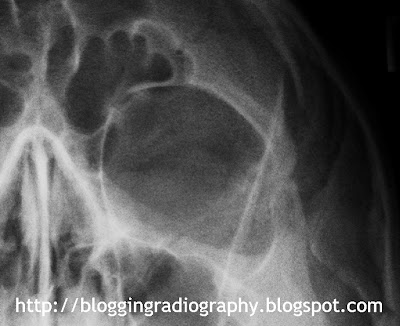

Orbits for MRI Clearance

It is still very common to receive orders for patients who need MRI exams, but require radiographic clearance to ensure there are no metal fragments in the eyes.  Routines vary from place to place, but reasons for performing this exam include metal/machine shop workers, history of foreign body removal from the eyes, or shrapnel injuries.  Our hospital only requires a water's view to include the orbits.  Here is a good example of what to look for, as well as what to do if the reading may be positive:

I didn't notice anything in the orbits at first, but when viewed on the high resolution screen of a Radiologist, you may see a small speck at the superiolateral aspect of the left orbit:

I thought this would be too far above the orbital rim to be considered a metal fragment in the eyeball, however due diligence should prevail because it may be metal regardless of where it's located.  When this happens, here's what you do:

1. Use a different cassette.  Dust and dirt may collect on the image plate and prevent light spread during processing for the affected area.

2. Clean your cassettes.  Most manufacturers recommend monthly cleaning of image plates, however, I may start cleaning them additionally before I perform any orbits for MRI clearance based on the repeat image:

As you can see on the magnified image, the white spot is no longer there, which means it was most likely dust... and the patient gets the MRI!